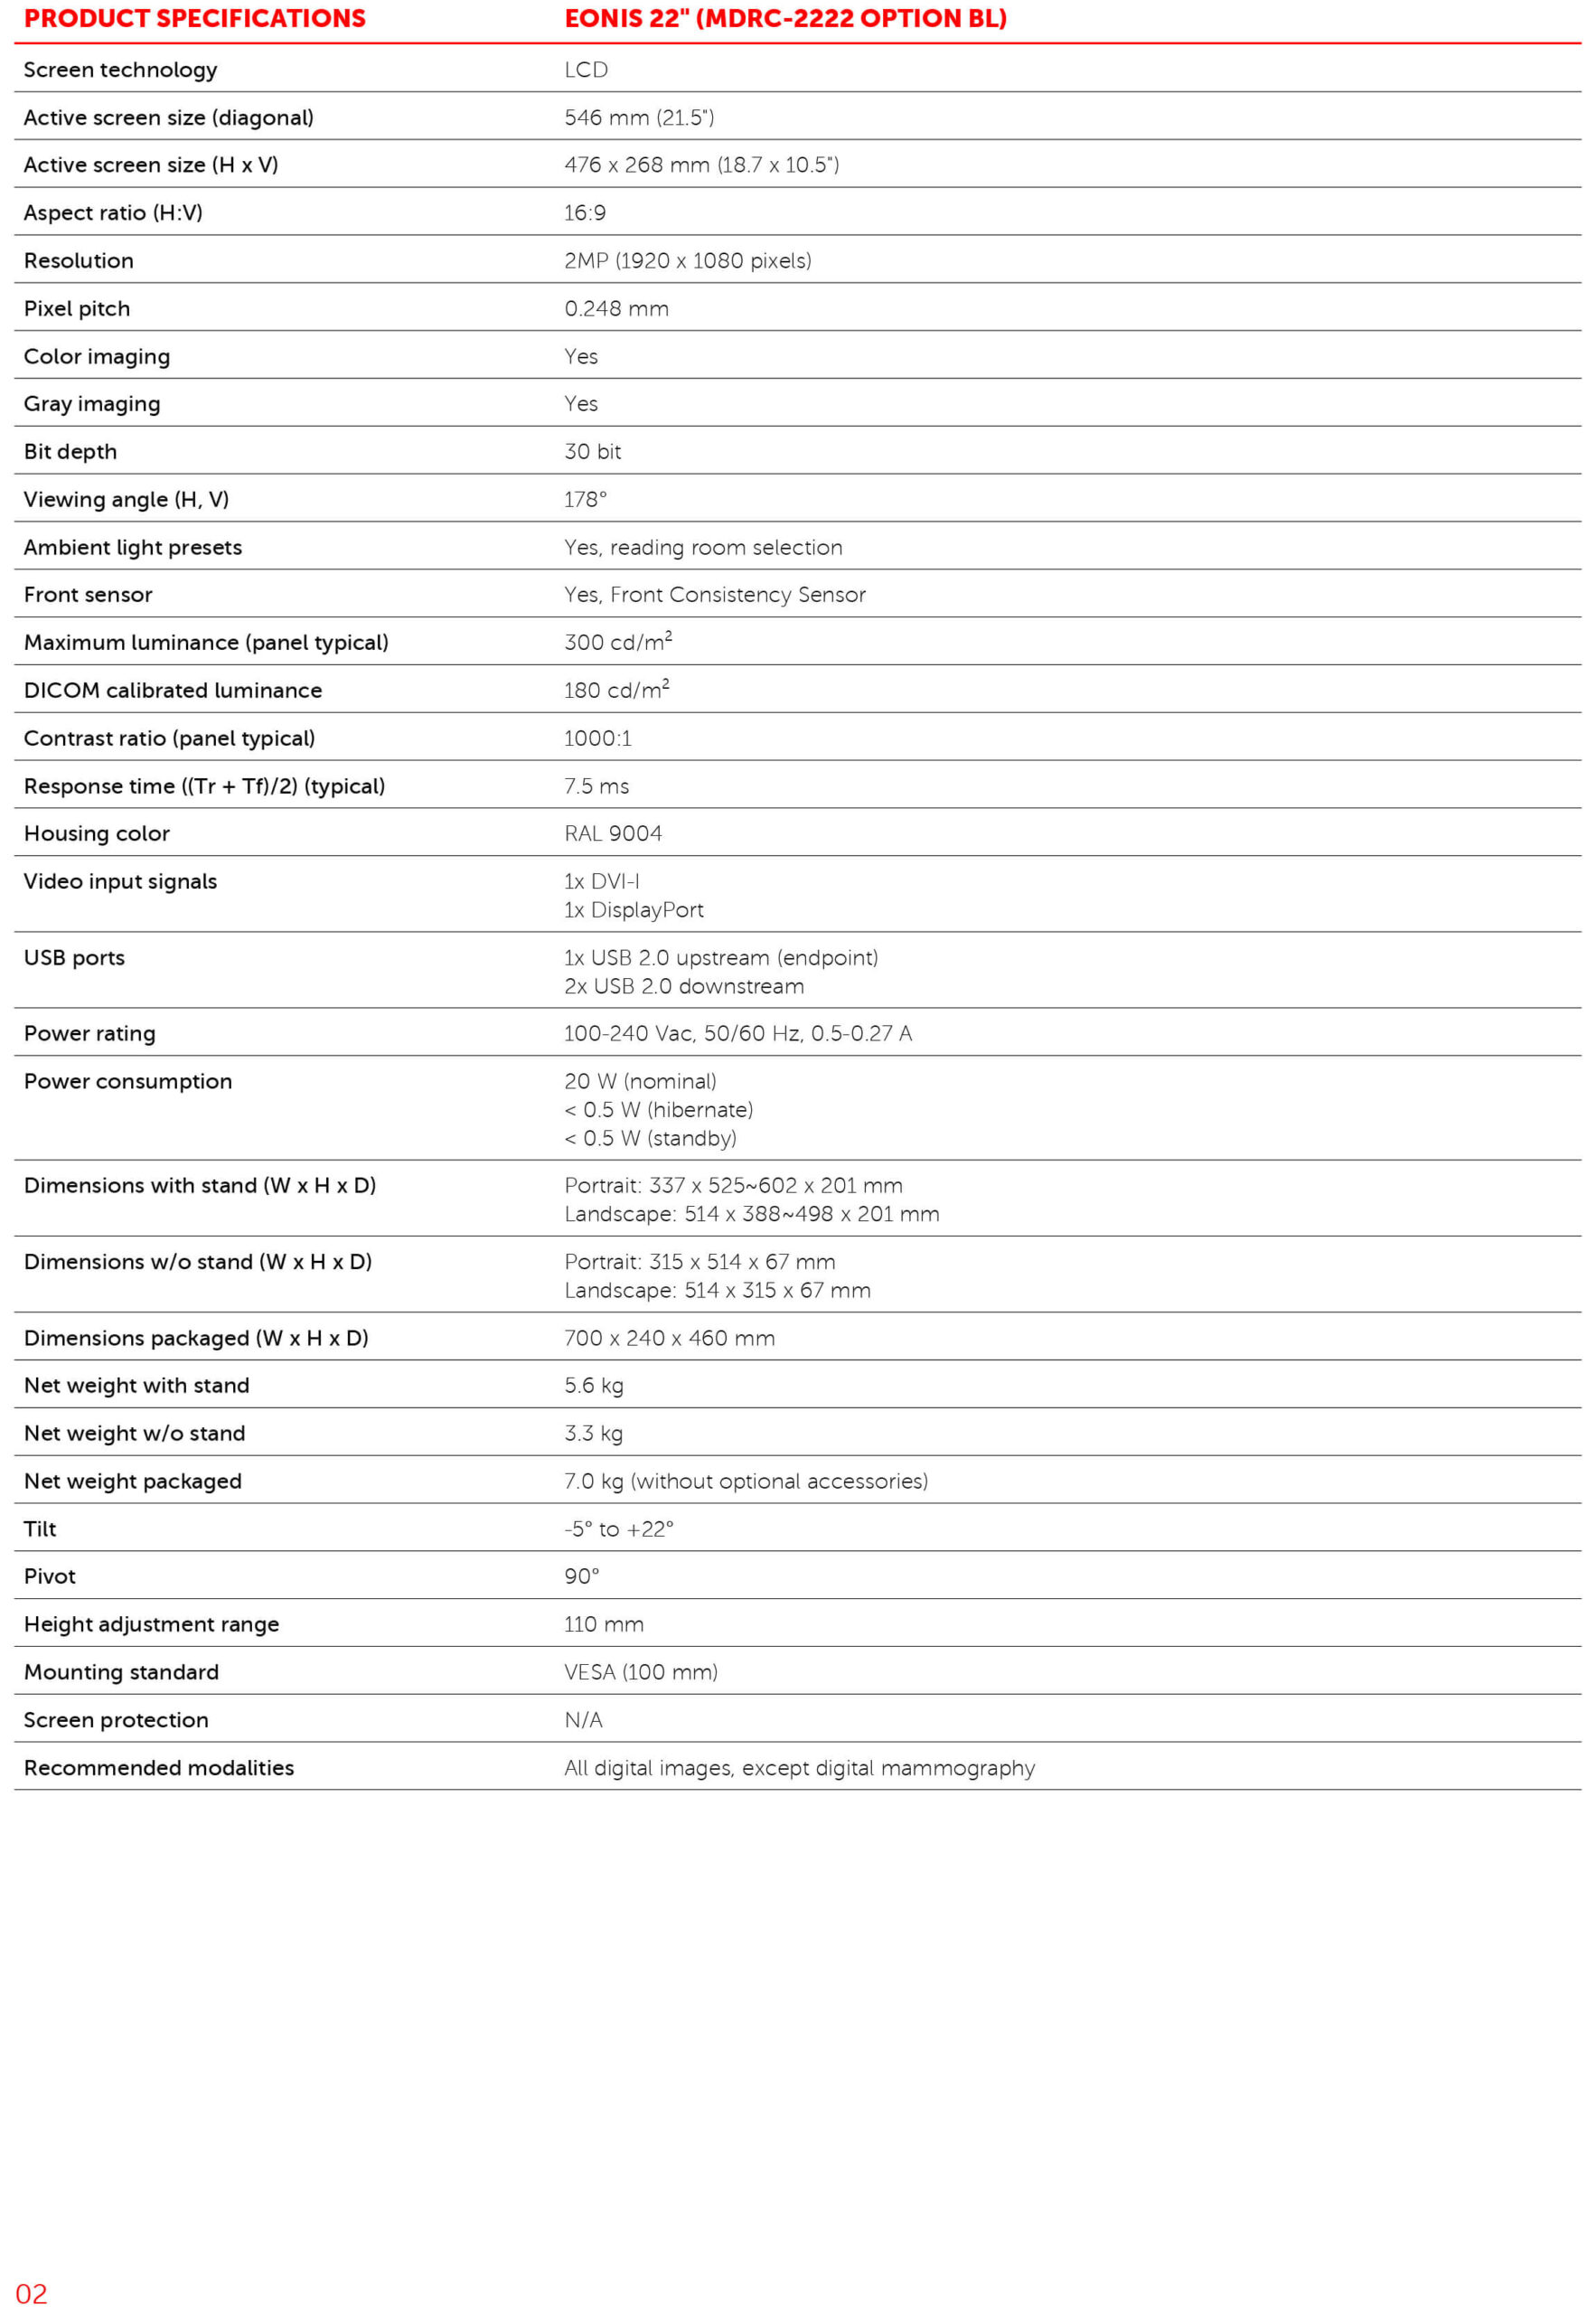

استاندارد DICOM

تصویربرداری دیجیتال و ارتباطات در پزشکی (Digital Imaging and Communications in Medicine – DICOM) یک استاندارد بینالمللی بوده که به منظور بهبود ارتباط تصاویر دیجیتال در رادیولوژی تنظیم شده است. یکی از کاربردهای استاندارد DICOM، تعریف یک تابع جهت تنظیم مقیاس خاکستری صفحه نمایشهای مورد استفاده در تصویربرداری پزشکی است. همچنین امکان ارتباط بین ایستگاههای کاری PACS، سیتی اسکنرها، تصویربردارهای MR، دیجیتالسازهای فیلم، آرشیوهای مشترک، پرینترهای لیزری، کامپیوترها و پردازندههای مرکزی مختلف را در بخش رادیولوژی فراهم میکند.

تکنولوژی IPS WideView

تکنولوژی IPS WideView یک معماری LCD پیشرفته است که حتی در صورت وجود زاویه دید گسترده، تصاویر را با رنگ سیاه یکنواختتر و کنتراست بهتر، نمایش میدهد. به طور خلاصه، با استفاده از این تکنولوژی امکان افزایش کیفیت تصویر، مشاهده جزئیات بسیار ظریف در نواحی تاریک تصویر و عملکرد سریع و کارآمد هنگام کار کردن با سیستمهای چند کاربره، وجود دارد.

تکنولوژی Consistency Sensor

به دلیل استفاده از یک سنسور تثبیت کننده تصویر (Consistency Sensor) در قسمت جلوی نمایشگر، با روشن شدن صفحه نمایش، کیفیت تصویر به طور اتوماتیک بهینه میشود.

سیستم پزشکی QAWeb

سیستم پزشکی QAWeb یک سرویس آنلاین بوده که به کاربران کمک میکند تا از تضمین کیفیت با درجه بالا اطمینان حاصل کنند. این سیستم به عنوان یک ابزار مبتنی بر وب میتواند برای کالیبراسیون، تضمین کیفیت و مدیریت سرمایه، به آسانی استفاده شود.